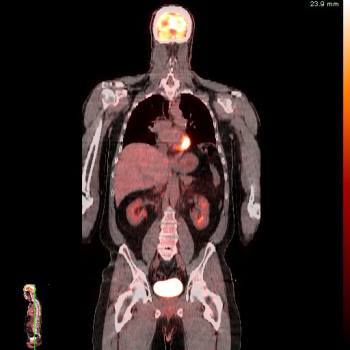

Tomografia por emision de positrones. Unidosis18-FDG (PET-CT). 921401 Idime (2024)

IDIME. Instituto de Diagnóstico Médico. Código de Convenio : 8915

BOGOTÁ

Sede Lago: Calle 76 No. 13 -46 / 13 -22

INCLUYE UNIDOSIS FDG-18

Venta directa: 4%